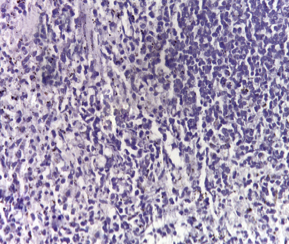

Immunohistochemical investigations

Immunohistochemical determination of the antibody specific for activated caspase-3 of the Control group showed negative results (fig. 1a) compared to the DMN group, as the activated caspase-3 was present in the cytoplasm of cells with morphology consistent with apoptosis (fig. 1b). While the groups injected with PRP and those administered orally with Qeurcetin showed negative results (fig. 1c and fig. 1d respectively).

Fig. 1(a-d): Immunohistochemical determination of the antibody specific for activated caspase-3 in splenic tissue, (a) Normal control showed a negative reaction, (b) DMN group showed a positive reaction, (c) PRP group showed negative reaction and (d) Qeurcetin group showed negative reaction (a-d X100)